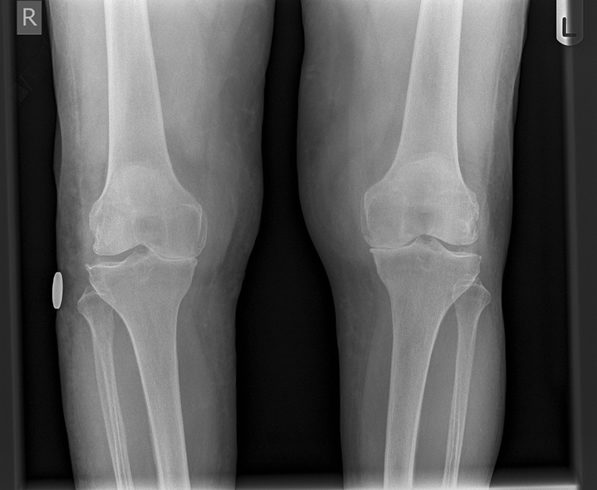

What does this x-ray show?

This is an AP bilateral knee radiograph of unknown patient unknown date that shows signs consistent with osteoarthritis: There is loss of joint space in the medial compartment of both knees, seemingly more severe on the right than the left. Subchondral sclerosis is visible on the proximal tibia in both knees, with subchondral cysts visible on the left proximal tibia and right distal femur. There also appears to be bilateral osteophyte formation. There is an unknown object on the right leg that appears to be spherical and metallic. In summary, this is a bilateral knee radiograph consistent with a diagnosis of osteoarthritis.

TLDR: All LOSS signs visible –> OA, worse in the medial compartment, present in the lateral. Unknown object on right leg.